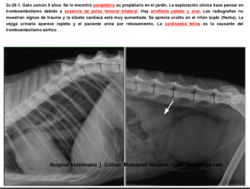

gato parapléjico por tromboembolismo aórtico.

Se muestran sus imágenes de resonancia magnética.